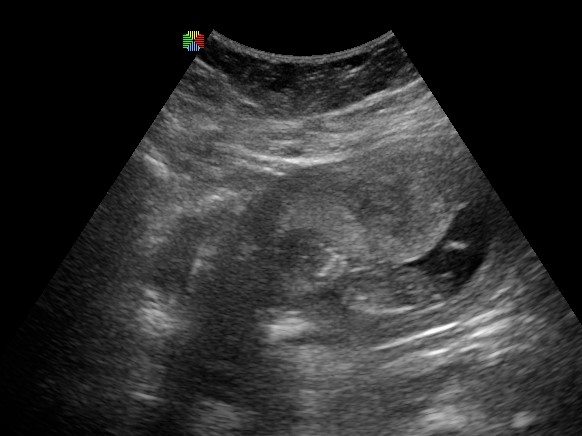

tady je fotka,jinou nemam ,blbě se to prej fotilo

to je z toho velkyho ultrazvuku

[1044762] Jo, ale hoví si tam hezky:-)...

[1044776] me říkal dr ze tam byla i placenta,ze zakryvala hlavicku trosku...uz se tesim na dalsi ko.az uvidim mimi...